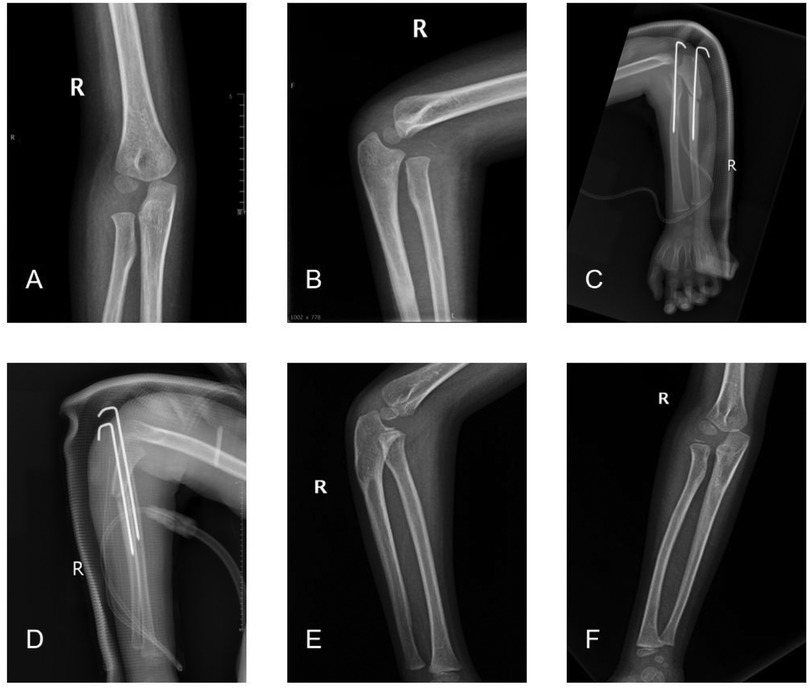

Objective: The aims of this study were to review our cases of missed Monteggia fracture treated by open reduction of the radial head with or without ulnar osteotomy and to investigate the necessity of ulnar osteotomy in surgical treatment of missed Monteggia fracture. Materials and methods: The children were divided into 2 groups according to the surgical methods: patients in group A were treated with Kirschner wire or external fixation after ulnar osteotomy and Kirschner wire fixation after humeroradial joint open reduction. Patients in group B were treated with open reduction of humeroradial joint fixed with Kirschner's wire, and ulna osteotomy was not performed. The imaging results of the most recent postoperative follow-up were evaluated using Nakamura grading criteria, and the elbow function was evaluated using Mayo elbow function score. Results: There were 53 patients in group A and 14 patients in group B. The mean age of children in group A was older than that in group B and the delay time of diagnosis and treatment in group A was longer than that in group B. There was no significant difference in the proportion of excellent postoperative Nakamura score between group A and group B (p>0.05). There was no significant difference in Mayo score of elbow joint after operation between group A and group B (P>0.05). In group A, complications of children were postoperative dislocation of humeroradial joint, broken Kirschner wire of humeroradial joint, occasional mild pain in the elbow joint and the Kirschner wire ends penetrating the subcutaneous tissue which were treated through surgery. In Group B, complications of children were postoperative dislocation of humeroradial joint, broken Kirschner wire of humeroradial joint and myositis ossificans. Conclusion: Ulnar osteotomy is not necessary for all children with missed Monteggia fracture. Open reduction of the humeroradial joint followed by Kirschner wire fixation can be considered as a surgical option for that younger patients with a short duration of delay.